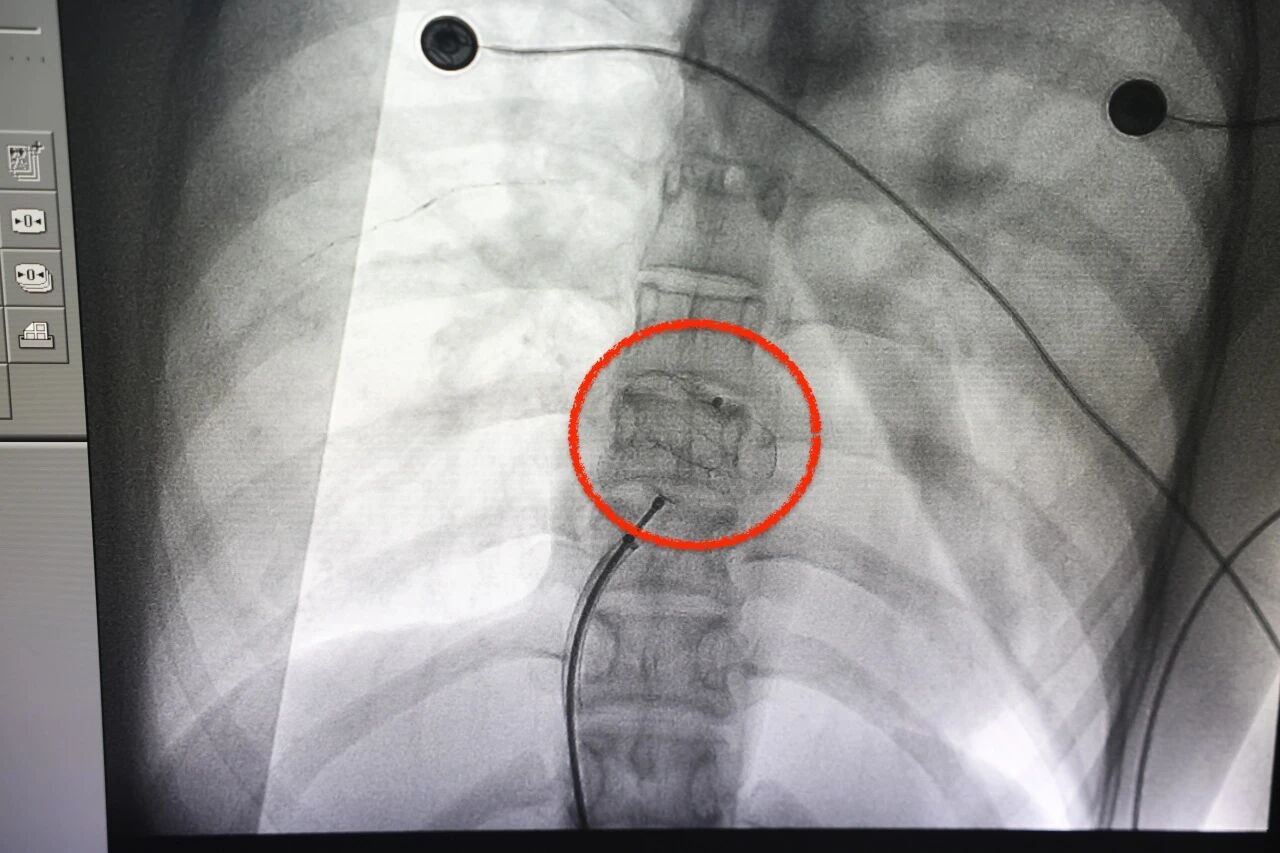

手术全程很顺利,医生通过导管将封堵器精准送到心脏缺损处,轻轻一释放,把这个「大漏洞」牢牢补上了。

术后复查彩超显示,心脏没有残余分流,瓣膜功能正常,心包也没有积液,恢复情况十分理想,很快就能出院回归校园。